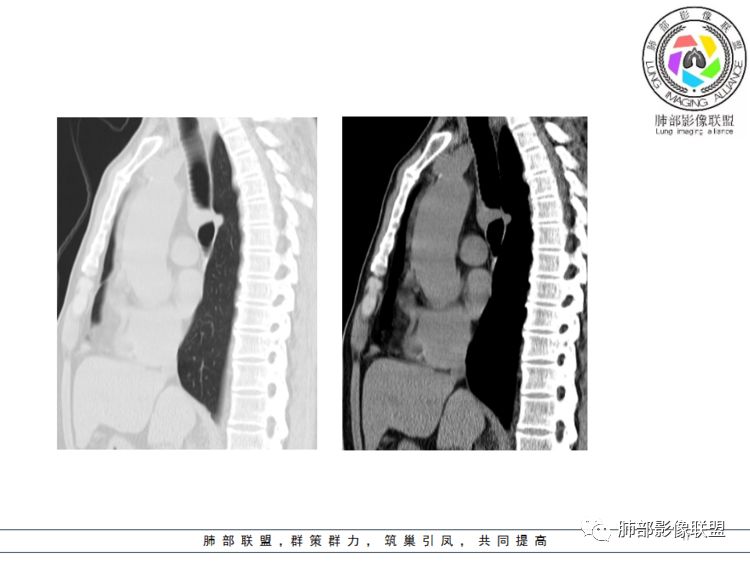

南边分析:针对本例,病灶跨气管壁内外生长,常规跨内外的有:恶性肿瘤为主,其次就是神经源性、平滑肌瘤;常规的思维:跨内外就要看结构的变化气管的优势在于软骨相对密度高,而且成C型

我们如何分析这个病例?冠状位:软骨密度稍高;病灶区软骨部分区域不连续,外围连续,提示病灶推移为主,不是破坏为主;如果破坏,应该这些软骨显示不清,移位不明显

病灶从软骨见推移开,跨内外,因此定在良性。恶性是侵犯,破坏为主,如果破坏,应该这些软骨显示不清,移位不明显,不是推移为主这例病变定在良性,我们就要考虑:1、软骨之间的平滑肌来源;2、神经源性